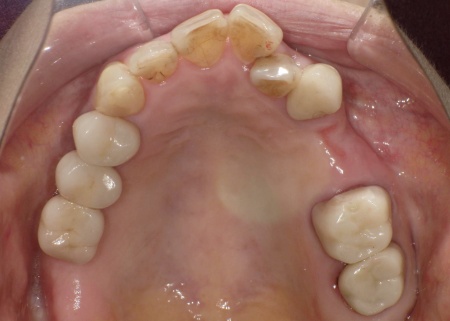

今回は審美性を考慮して、金属のバネではなく樹脂の留め具で固定する部分入れ歯「ノンクラスプデンチャー」を提案し、同意いただきました。

ノンクラスプデンチャーの留め具は歯茎に近い色をしているため、目立ちにくいのが特徴です。

3ヶ月間の経過観察後、傷が治癒したことが確認できたため、ノンクラスプデンチャーを作製するための型取りを行いました。

また、噛み合わせの記録を取ったり、周囲の歯に馴染む色調の人工歯を選んだりなど、患者様によりぴったりと合う入れ歯に仕上げています。

約3週間後、完成した入れ歯を装着し、使用感や見た目に問題がないことを確認して、治療を終了しました。